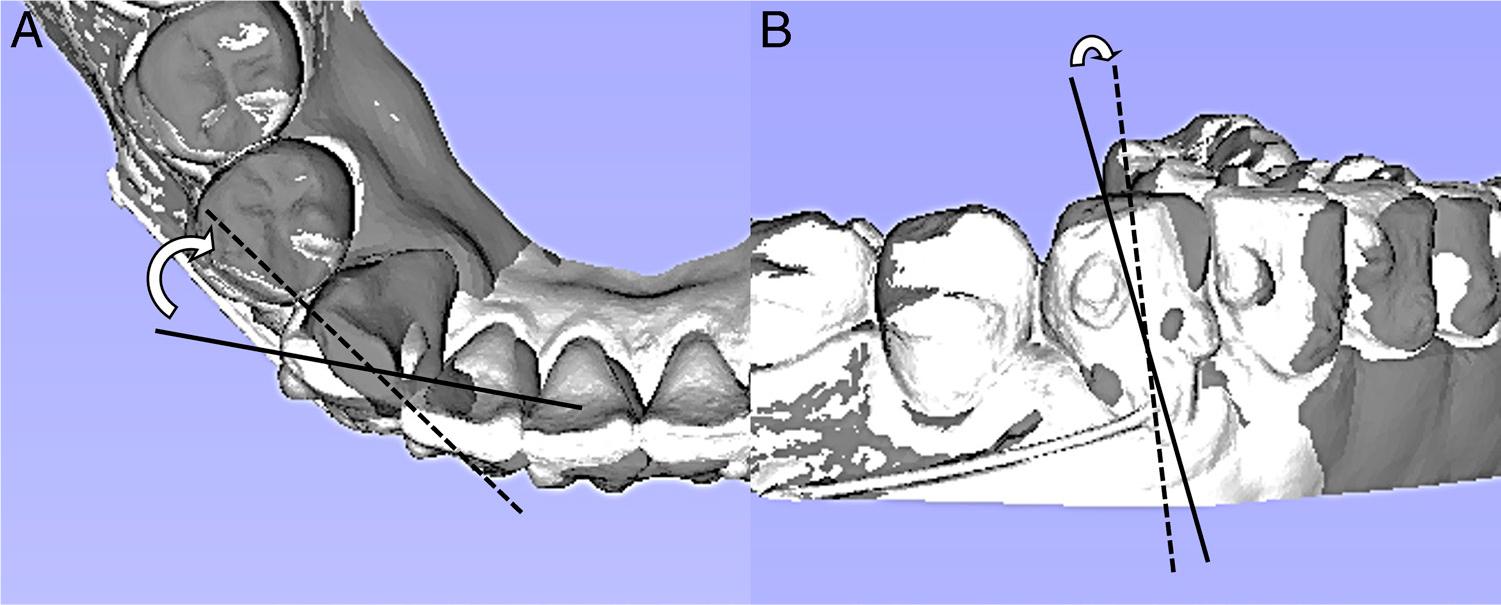

Tooth movements between the treatment courses were analysed using the surface registration function of the 3D Slicer program. Since the first and second molars were not moved, their occlusal surfaces were used for surface registration. The planned tooth movement was compared on virtual setups with the actual achieved movement. To measure the planned and achieved movement, the initial model of an aligner treatment course was superimposed with the planned and achieved models, respectively. Canine rotation was calculated as the angle between the lines connecting the mesial and distal contact points. Similarly, mesiodistal angulation, as an indirect measure of root movement, was assessed as the angle between the facial axes of the clinical crowns (Figure 13). Treatment accuracy was evaluated by calculating the ratio of achieved movement to planned movement. Treatment efficiency was measured by determining the rate of tooth movement over the treatment period. Additionally, the achieved movements and the efficiency of the bracketless NiTi treatment were also evaluated. The total rotation and angulation achieved were 34.2° and 22.6°, respectively (Table II). Of the total movements, the aligner therapy accounted for 30.8° of rotation and 18.8° of angulation change. Specifically, a 7.4° rotation and a 3.3° angulation were achieved during the 4.5 months of the aligner-only treatment period. In contrast, the hybrid approach led to a 23.4° rotation and 15.5° angulation change over 5.5 months. Appliance accuracy and efficiency were enhanced more than two to four times using the hybrid approach.

Rotation and angulation measurements between the initial and the predicted or achieved models. The white model serves as the reference, while the dark model represents either the planned or achieved state. Reference lines are depicted with plain lines, and target lines as dotted lines. Arrows indicate the angles between the reference lines. A, Rotation. B, Angulation.